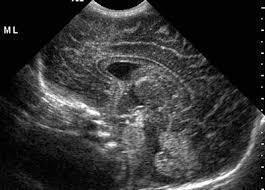

PEDİATRİK BEYİN ULTRASONU

Transfontanel ultrason yeni doğan bebeklerde sıklıkla kullanılmakla birlikte bebeklerin kafa kemikleri kapanana kadar (yaklaşık 6-9 ay) yapılabilir.

Bu inceleme ile kafa kemiklerinin henüz kapanmayan alanları pencere olarak kullanılarak beyin yapıları, damarlar, beyin omurilik sıvısı ve beyin zarları değerlendirilir. Yeni doğan bebeklerde özellikle prematürite olması durumunda beyin gelişiminin normal olup olmadığı değerlendirilir. Prematür bebeklerde beyin içi kanama olasılığı daha yüksektir. Bu durumda da ultrason inceleme olası kanamanı yeri, büyüklüğü, çevre dokulara basısı gibi konularda fikir verir. Yine beyin omurilik sıvısının (BOS) artış gösterdiği durumlarda bu artışın derecelendirilmesi ve tedavinin planlanması için en uygun görüntüleme yöntemidir. Beyin içerisinden doğumsal olarak gelişen kitleleri değerlendirmek için de öncelikle ultrason inceleme kullanılır.